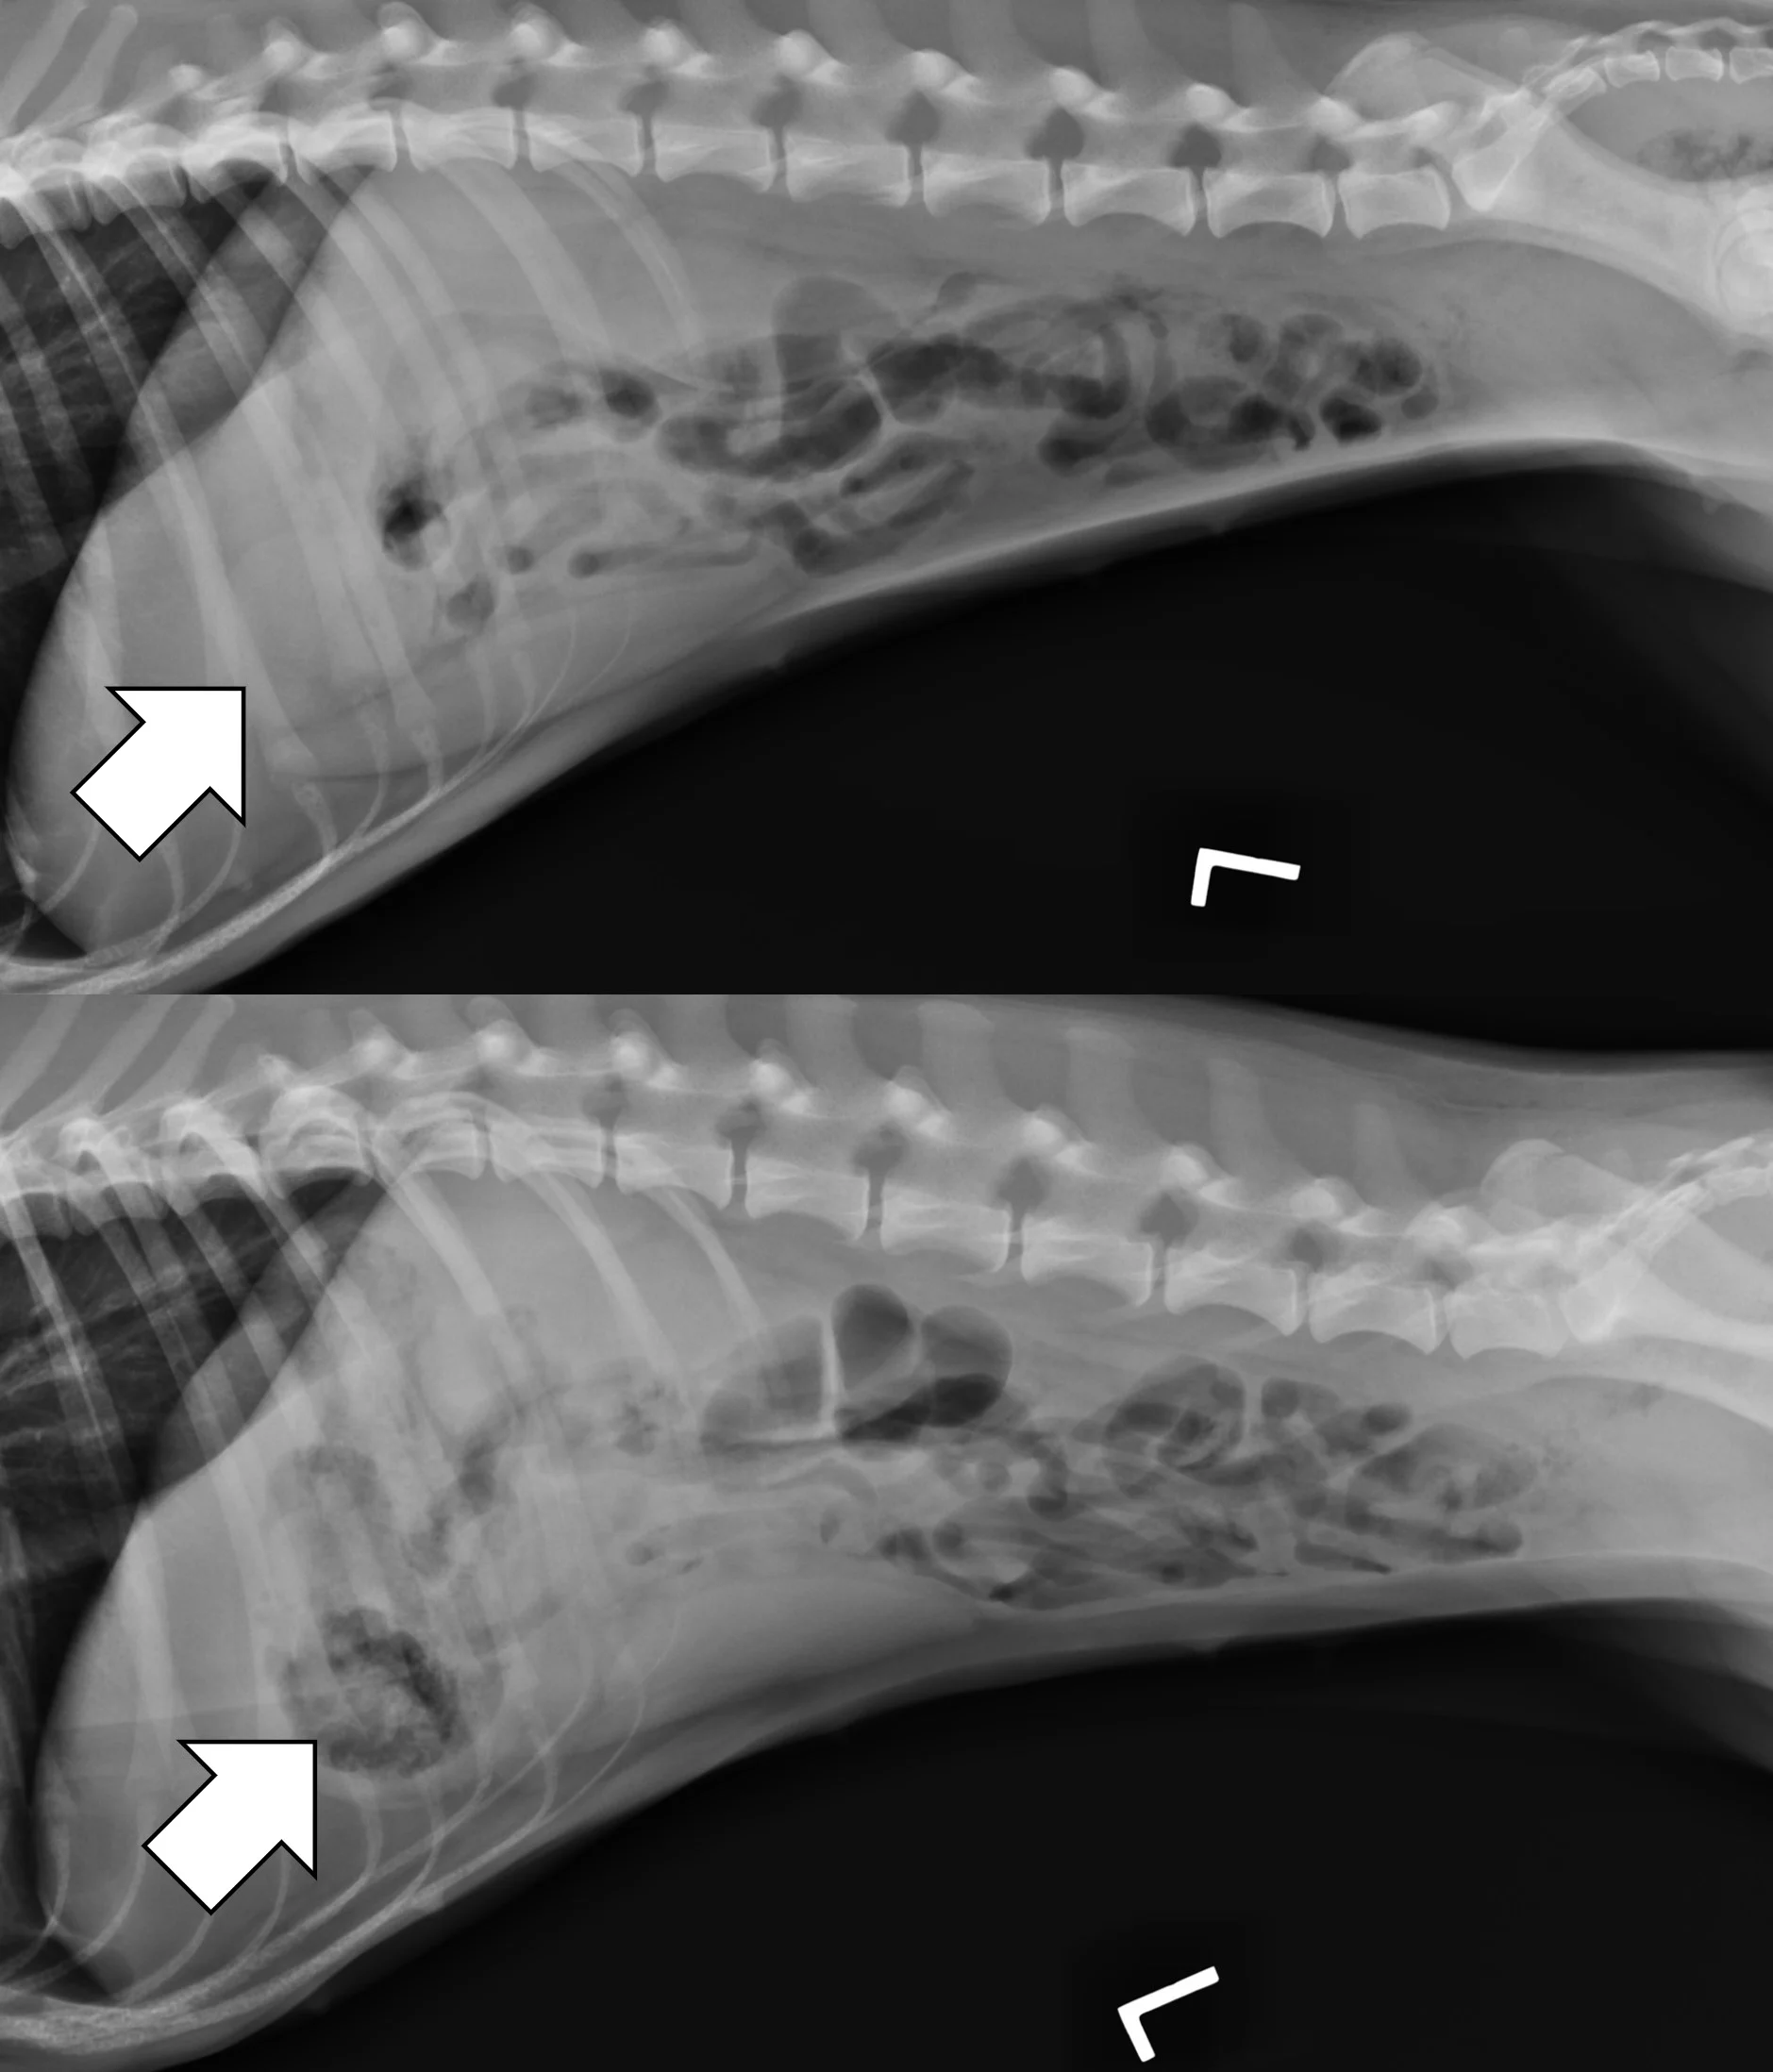

Right lateral radiographs of a 6-month-old spayed seal point crossbreed cat with a surgically confirmed acute linear foreign body (hair entangled in hair ties) obstruction. The small bowel is bunched in the midabdomen, making the plicated small bowel difficult to see (top, arrows). Normal small bowel displaces after compression with a wooden spoon, but the plicated bowel remains stationary and is easier to see (bottom, arrows).

In some patients, especially those that are obese, the small bowel loosely bunches, raising concern for a linear foreign body obstruction. Obtaining a lateral and/or ventrodorsal radiograph while gently compressing the region of concern with a wooden spoon can help differentiate physiologically bunched small intestine (easily disperses) from plicated bowel (does not disperse).